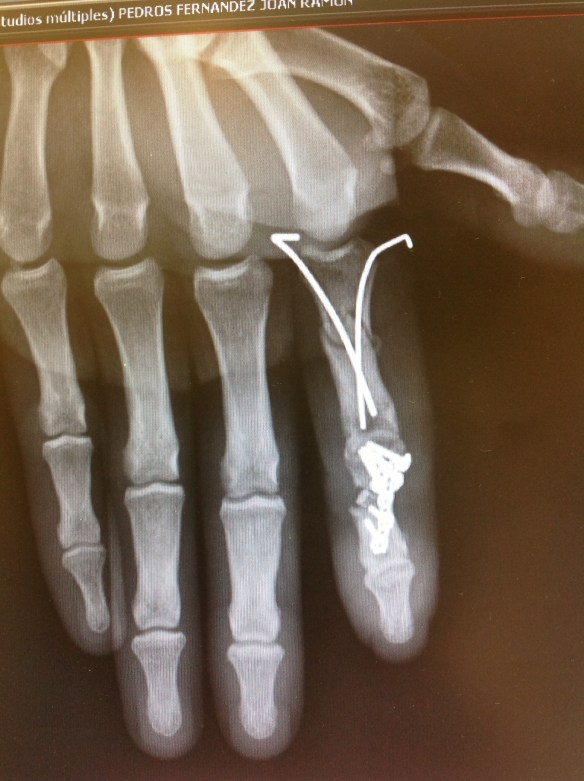

Paciente d 19 años que ingresó en nuestro centro afecto de Fractura de F2 del pulgar, fractura transversa de la F1 del índice, fractura conminuta de la F2 del índice con afectación del aparato extensor al mismo nivel.

Se procedió a síntesis anterógrada de la F1 con 2 agujas de Kirshner introducidas con la articulación metacarpofalángica en flexión máxima para no limitar la rehabilitación precoz.no coloqué placa de síntesis pues tengo comprobado que en la F1 las placas dan lugar a gran número de rigideces que obligan a su retarda y a tenolisis. En la F2 conminuta procedí a colocar placa con injerto de radio, en lidera rotación radial para facilitar la pinza término-terminal de un índice que por la lesión del aparato extensor asociada ya se preveía que tendría poca mobilidad de IFD. Se inició kinesiterapia activa autoasistida a los 3días postop.

Se retiraron las agujas tras consolidación de la F1.